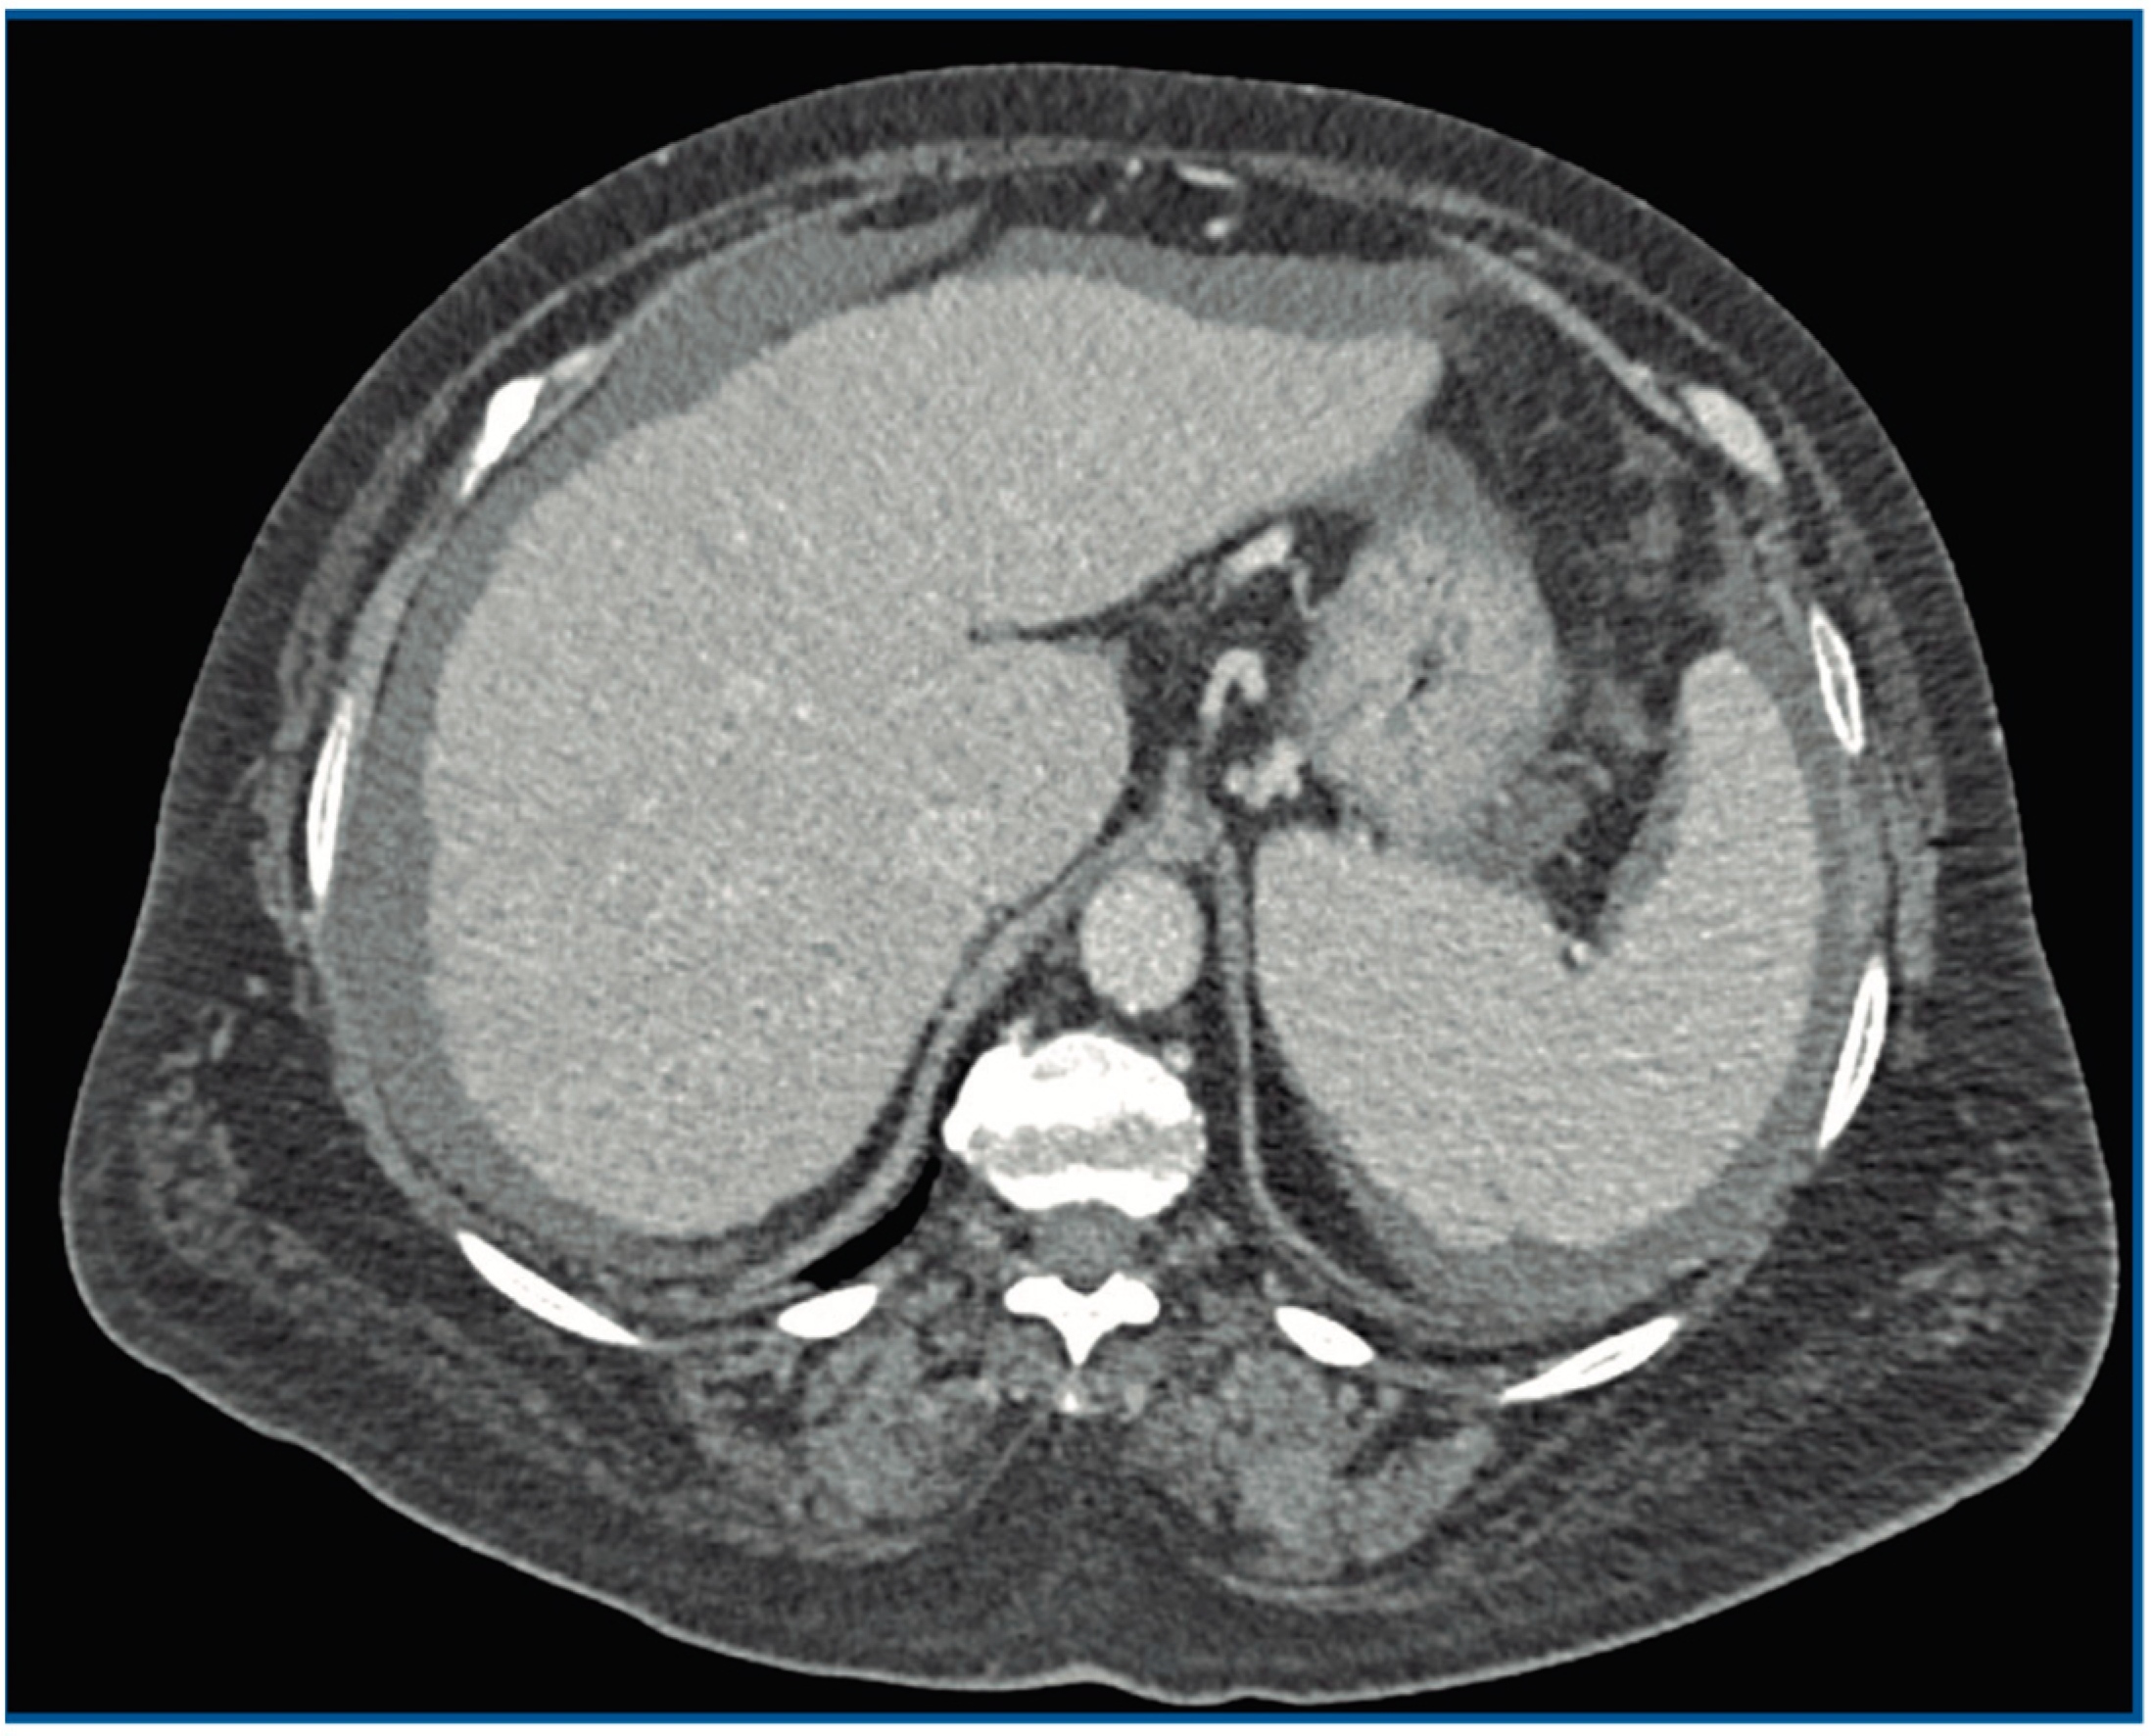

| Present case, 2021 | Female, 60 | Total hip arthroplasty | Cirrhosis | DAIR. Second DAIR after 10 d | Daptomycin, cloxacillin and ceftazidime 4 d. Cefotaxime and metronidazole 2 w Amoxicillin 4 w |